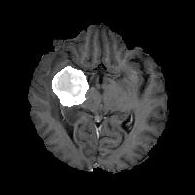

We first introduce a method for connecting the output of a CNN to an ACM, yielding a model for the precise delineation of lesions, to which we refer as Deep Active Lesion Segmentation (DALS) (Figure 4). We then go further to introduce a truly unified framework (Figure 5) that bridges the gap between ACMs and CNNs by leveraging a novel, automatically differentiable level-set ACM with trainable parameters that allows for back-propagation of gradients and can be end-to-end trained along with a backbone CNN from scratch, without any CNN pre-training. The ACM is initialized directly by the CNN and utilizes an energy functional that is locally-tunable by the backbone CNN, through 2D feature maps. Thus, our work overcomes the big hurdle of fully automating the powerful ACM approach to image segmentation. We have applied our proposed framework to the task of building segmentation in aerial images (Figure 6).

Deep Active Lesion Segmentation

[45]: Lesion segmentation is an important problem in computer-assisted diagnosis that remains challenging due to the prevalence of low contrast, irregular boundaries that are unamenable to shape priors. We introduce Deep Active Lesion Segmentation (DALS), a fully automated segmentation framework that leverages the powerful nonlinear feature extraction abilities of FCNs and the precise boundary delineation abilities of ACMs. Our DALS framework benefits from an improved level-set ACM formulation with a per-pixel-parameterized energy functional and a novel multiscale encoder-decoder CNN that learns an initialization probability map along with parameter maps for the ACM. We evaluate our lesion segmentation model on a new Multiorgan Lesion Segmentation (MLS) dataset that contains images of various organs, including brain, liver, and lung, across different imaging modalities—MR and CT. Our results demonstrate favorable performance compared to competing methods, especially for small training datasets. -